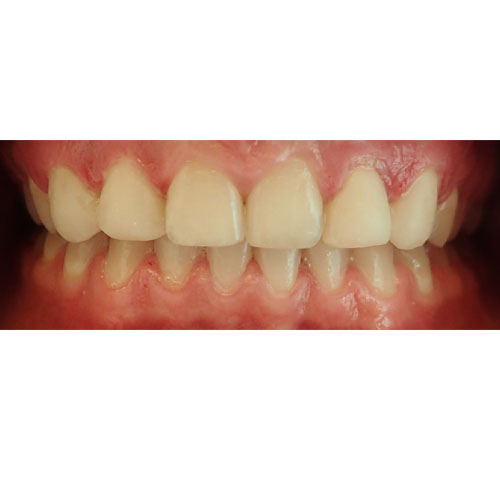

Nasze rezultaty